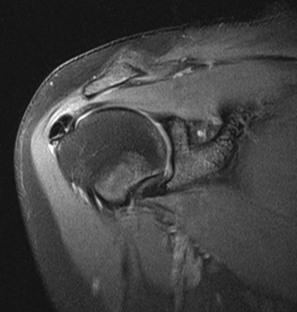

The “hourglass” biceps tendon describes a condition featuring marked tendinosis and hypertrophy isolated to the intraarticular portion of the long bicipital tendon, which prevents the tendon from sliding into the bicipital groove during elevation of the arm.131 Entrapment of the long bicipital tendon causes a mechanical block and pain. This condition occurs most often in association with a full-thickness tear of the rotator cuff, although entrapment occurring in association with partial-thickness rotator cuff tears has been described in case reports as well. Patients present with anterior arm pain and loss of passive elevation of the arm averaging about 10 to 20 degrees. The condition is treated with resection of the abnormal segment and tenodesis of the biceps tendon followed by appropriate treatment of any concomitant injury of the rotator cuff. MRI will show marked tendinosis and thickening limited to the intraarticular portion of the biceps tendon (Fig. 44-33) and is often associated with either a partial- or full-thickness rotator cuff tear.